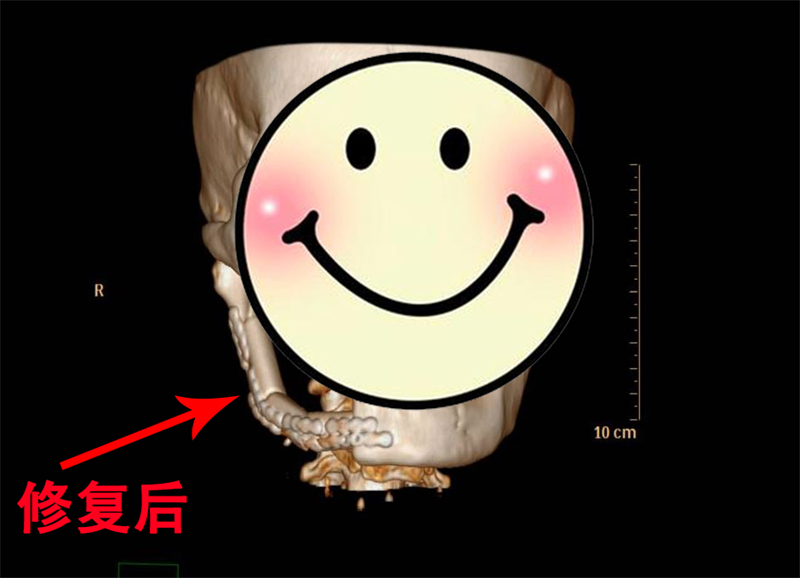

随后,手术团队运用显微外科技术,在高倍显微镜下小心翼翼完成血管吻合,确保移植腓骨血供通畅,为患者恢复面容与功能带去双重曙光。

在团队的悉心照料下,移植腓骨成功成活,面部肿胀逐步消退,张口、咀嚼功能稳步恢复。